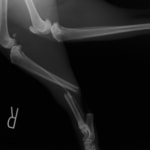

機器

Arthrex社のターゲティングデバイスを用いてピンニングの位置を調整することで、確実な固定を行っています。当院ではこの手術器具以外にも、人の手術にも使用される様々な器具を導入し、手術精度を高め、また医療メーカーと新しい器具の開発、試作にも取り組んでおります。